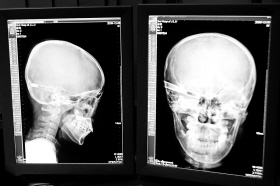

“還是先做個X光透視,看一下箭桿到底有多深!毖劭漆t(yī)生緊急趕到CT室查看,和放射科的幾位醫(yī)生共同研究后,決定先讓小沖做X光透視。

“如果再用點力,就從后腦穿出來了!”由于小沖無法移動,醫(yī)生拿來移動插座,將透視的光板放在小沖的移動病床上,透視后讓在場的醫(yī)生都吃了一驚:箭桿直接穿過了大腦和小腦,箭尖兒直抵后顱骨,足足有10余厘米。